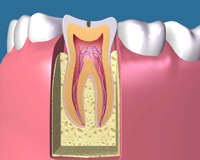

C0 表面が少しだけ溶けた軽度の虫歯です。ごく初期の場合は歯磨 きをすることで治る場合もあります。(歯の再石灰化) 削らないで様子をみます。 |

C1 虫歯の初期です。 ほとんど痛みがありませんので、麻酔をせず虫歯の部分を削 ってレジン製の詰め物(白いプラスティック)を入れて治療 は終わります。 |

歯の根の中は、中空になっていて、その中に神経や血管などが詰まっています。

虫歯などによって歯の神経に細菌が入り込んで炎症を起こすと、歯の神経は死んでしまいます。

深い虫歯などが原因で神経を取ったあと、根の中の中空部分をきれいにして処置をすることを根管治療と言います。